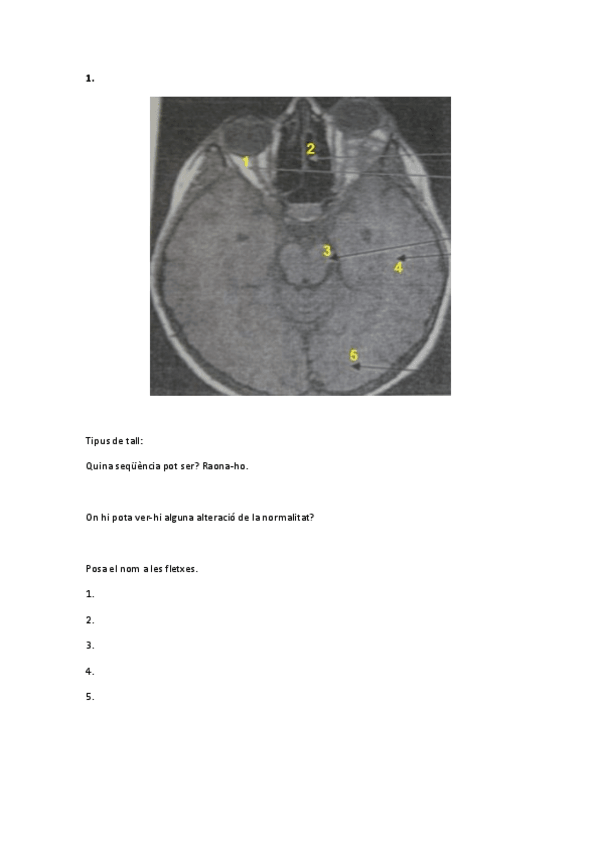

imagenes-2n-exam-rellenado.pdf

10 páginas